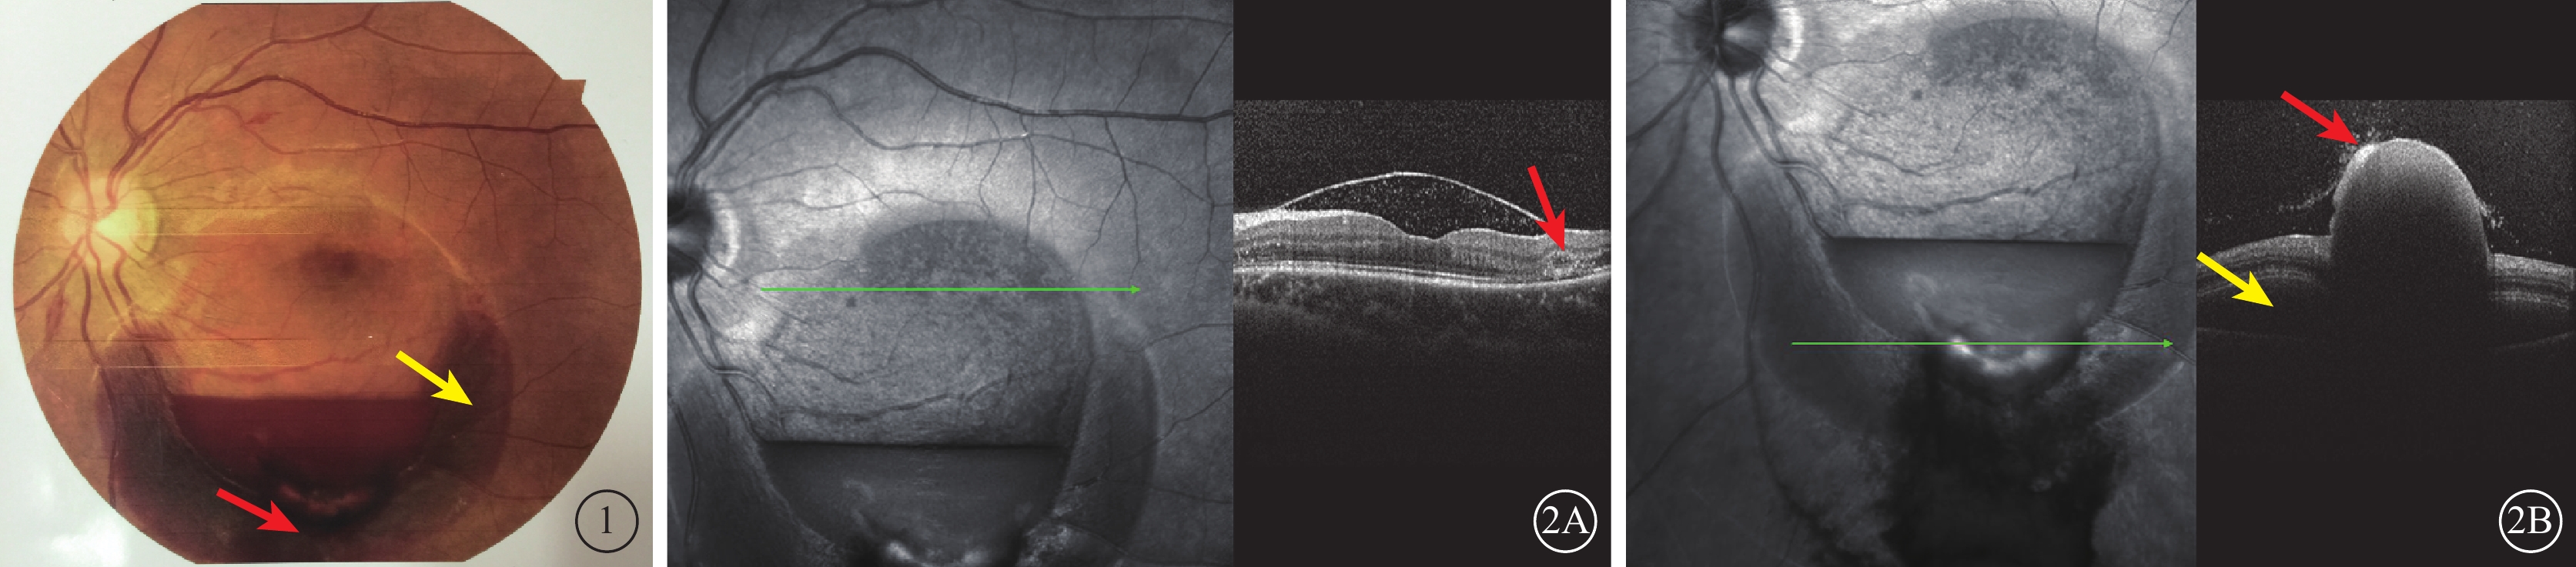

15只眼中,后極部黃斑區視網膜內界膜下出血10只眼。其中,視網膜前1~8個視盤直徑(DD)大小圓頂狀隆起,其邊緣可見視網膜淺層和(或)深層出血7只眼,其中伴少量玻璃體積血3只眼;視網膜前8~10 DD大小圓頂狀隆起,其邊緣可見視網膜淺層或深層出血和后極部視網膜點狀或火焰狀出血3只眼。視盤鼻側視網膜內界膜下出血1只眼,視網膜前1~2 DD大小的圓頂狀隆起,出血區邊緣視網膜淺層或深層出血。黃斑區視網膜深層出血2只眼。視網膜內界膜自行破裂致玻璃體積血2只眼。其中,1只眼為妊娠36周孕婦,因劇烈嘔吐后左眼視力下降2 d就診。黃斑區可見約10 DD大小圓頂狀隆起,下方1/2環狀視網膜下出血,其內可見淡血性視網膜前出血(內界膜下),出血灶1/2處可見液平面(圖1);出血區下方可見玻璃體腔相連的血凝塊,余視網膜平復。OCT檢查,下方環形出血區為視網膜神經上皮層出血,內界膜破裂,出血突出于玻璃體腔,視網膜深層層間出血(圖2)。

圖1

左眼彩色眼底像。視盤邊界清楚,黃斑區約10 DD大小出血區,下方1/2環狀視網膜下出血(黃箭),其內可見淡血性視網膜前出血,出血灶1/2處可見液平面;出血區下方可見與玻璃體腔相連的血凝塊(紅箭) 圖2 左眼OCT像。2A. 出血區液平上方可見內界膜隆起,其下為弱反射信號,內可見點狀中強反射信號;內界膜隆起邊緣可見視網膜深層出血(紅箭)。2B. 下方環形出血區可見出血部位在神經上皮層下出血(黃箭)及內界膜破裂,突出于玻璃體腔的血凝塊(紅箭)

圖1

左眼彩色眼底像。視盤邊界清楚,黃斑區約10 DD大小出血區,下方1/2環狀視網膜下出血(黃箭),其內可見淡血性視網膜前出血,出血灶1/2處可見液平面;出血區下方可見與玻璃體腔相連的血凝塊(紅箭) 圖2 左眼OCT像。2A. 出血區液平上方可見內界膜隆起,其下為弱反射信號,內可見點狀中強反射信號;內界膜隆起邊緣可見視網膜深層出血(紅箭)。2B. 下方環形出血區可見出血部位在神經上皮層下出血(黃箭)及內界膜破裂,突出于玻璃體腔的血凝塊(紅箭)

15只眼中,后極部黃斑區視網膜內界膜下出血10只眼。其中,視網膜前1~8個視盤直徑(DD)大小圓頂狀隆起,其邊緣可見視網膜淺層和(或)深層出血7只眼,其中伴少量玻璃體積血3只眼;視網膜前8~10 DD大小圓頂狀隆起,其邊緣可見視網膜淺層或深層出血和后極部視網膜點狀或火焰狀出血3只眼。視盤鼻側視網膜內界膜下出血1只眼,視網膜前1~2 DD大小的圓頂狀隆起,出血區邊緣視網膜淺層或深層出血。黃斑區視網膜深層出血2只眼。視網膜內界膜自行破裂致玻璃體積血2只眼。其中,1只眼為妊娠36周孕婦,因劇烈嘔吐后左眼視力下降2 d就診。黃斑區可見約10 DD大小圓頂狀隆起,下方1/2環狀視網膜下出血,其內可見淡血性視網膜前出血(內界膜下),出血灶1/2處可見液平面(圖1);出血區下方可見玻璃體腔相連的血凝塊,余視網膜平復。OCT檢查,下方環形出血區為視網膜神經上皮層出血,內界膜破裂,出血突出于玻璃體腔,視網膜深層層間出血(圖2)。

圖1

左眼彩色眼底像。視盤邊界清楚,黃斑區約10 DD大小出血區,下方1/2環狀視網膜下出血(黃箭),其內可見淡血性視網膜前出血,出血灶1/2處可見液平面;出血區下方可見與玻璃體腔相連的血凝塊(紅箭) 圖2 左眼OCT像。2A. 出血區液平上方可見內界膜隆起,其下為弱反射信號,內可見點狀中強反射信號;內界膜隆起邊緣可見視網膜深層出血(紅箭)。2B. 下方環形出血區可見出血部位在神經上皮層下出血(黃箭)及內界膜破裂,突出于玻璃體腔的血凝塊(紅箭)

圖1

左眼彩色眼底像。視盤邊界清楚,黃斑區約10 DD大小出血區,下方1/2環狀視網膜下出血(黃箭),其內可見淡血性視網膜前出血,出血灶1/2處可見液平面;出血區下方可見與玻璃體腔相連的血凝塊(紅箭) 圖2 左眼OCT像。2A. 出血區液平上方可見內界膜隆起,其下為弱反射信號,內可見點狀中強反射信號;內界膜隆起邊緣可見視網膜深層出血(紅箭)。2B. 下方環形出血區可見出血部位在神經上皮層下出血(黃箭)及內界膜破裂,突出于玻璃體腔的血凝塊(紅箭)